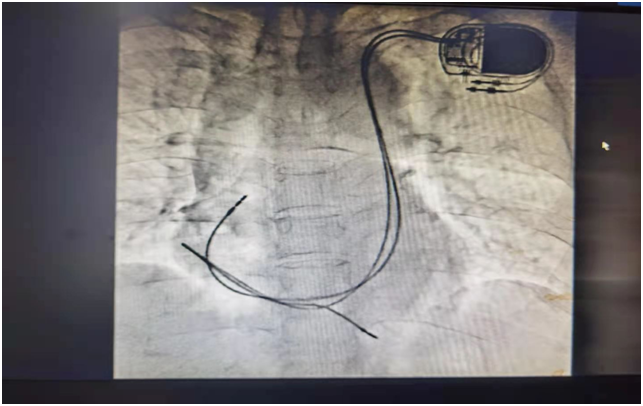

这就是安置好的双腔起搏器位置图.

双腔心脏起搏器手术中8月10日,邹祎主任团队为该患者植入了永久双腔